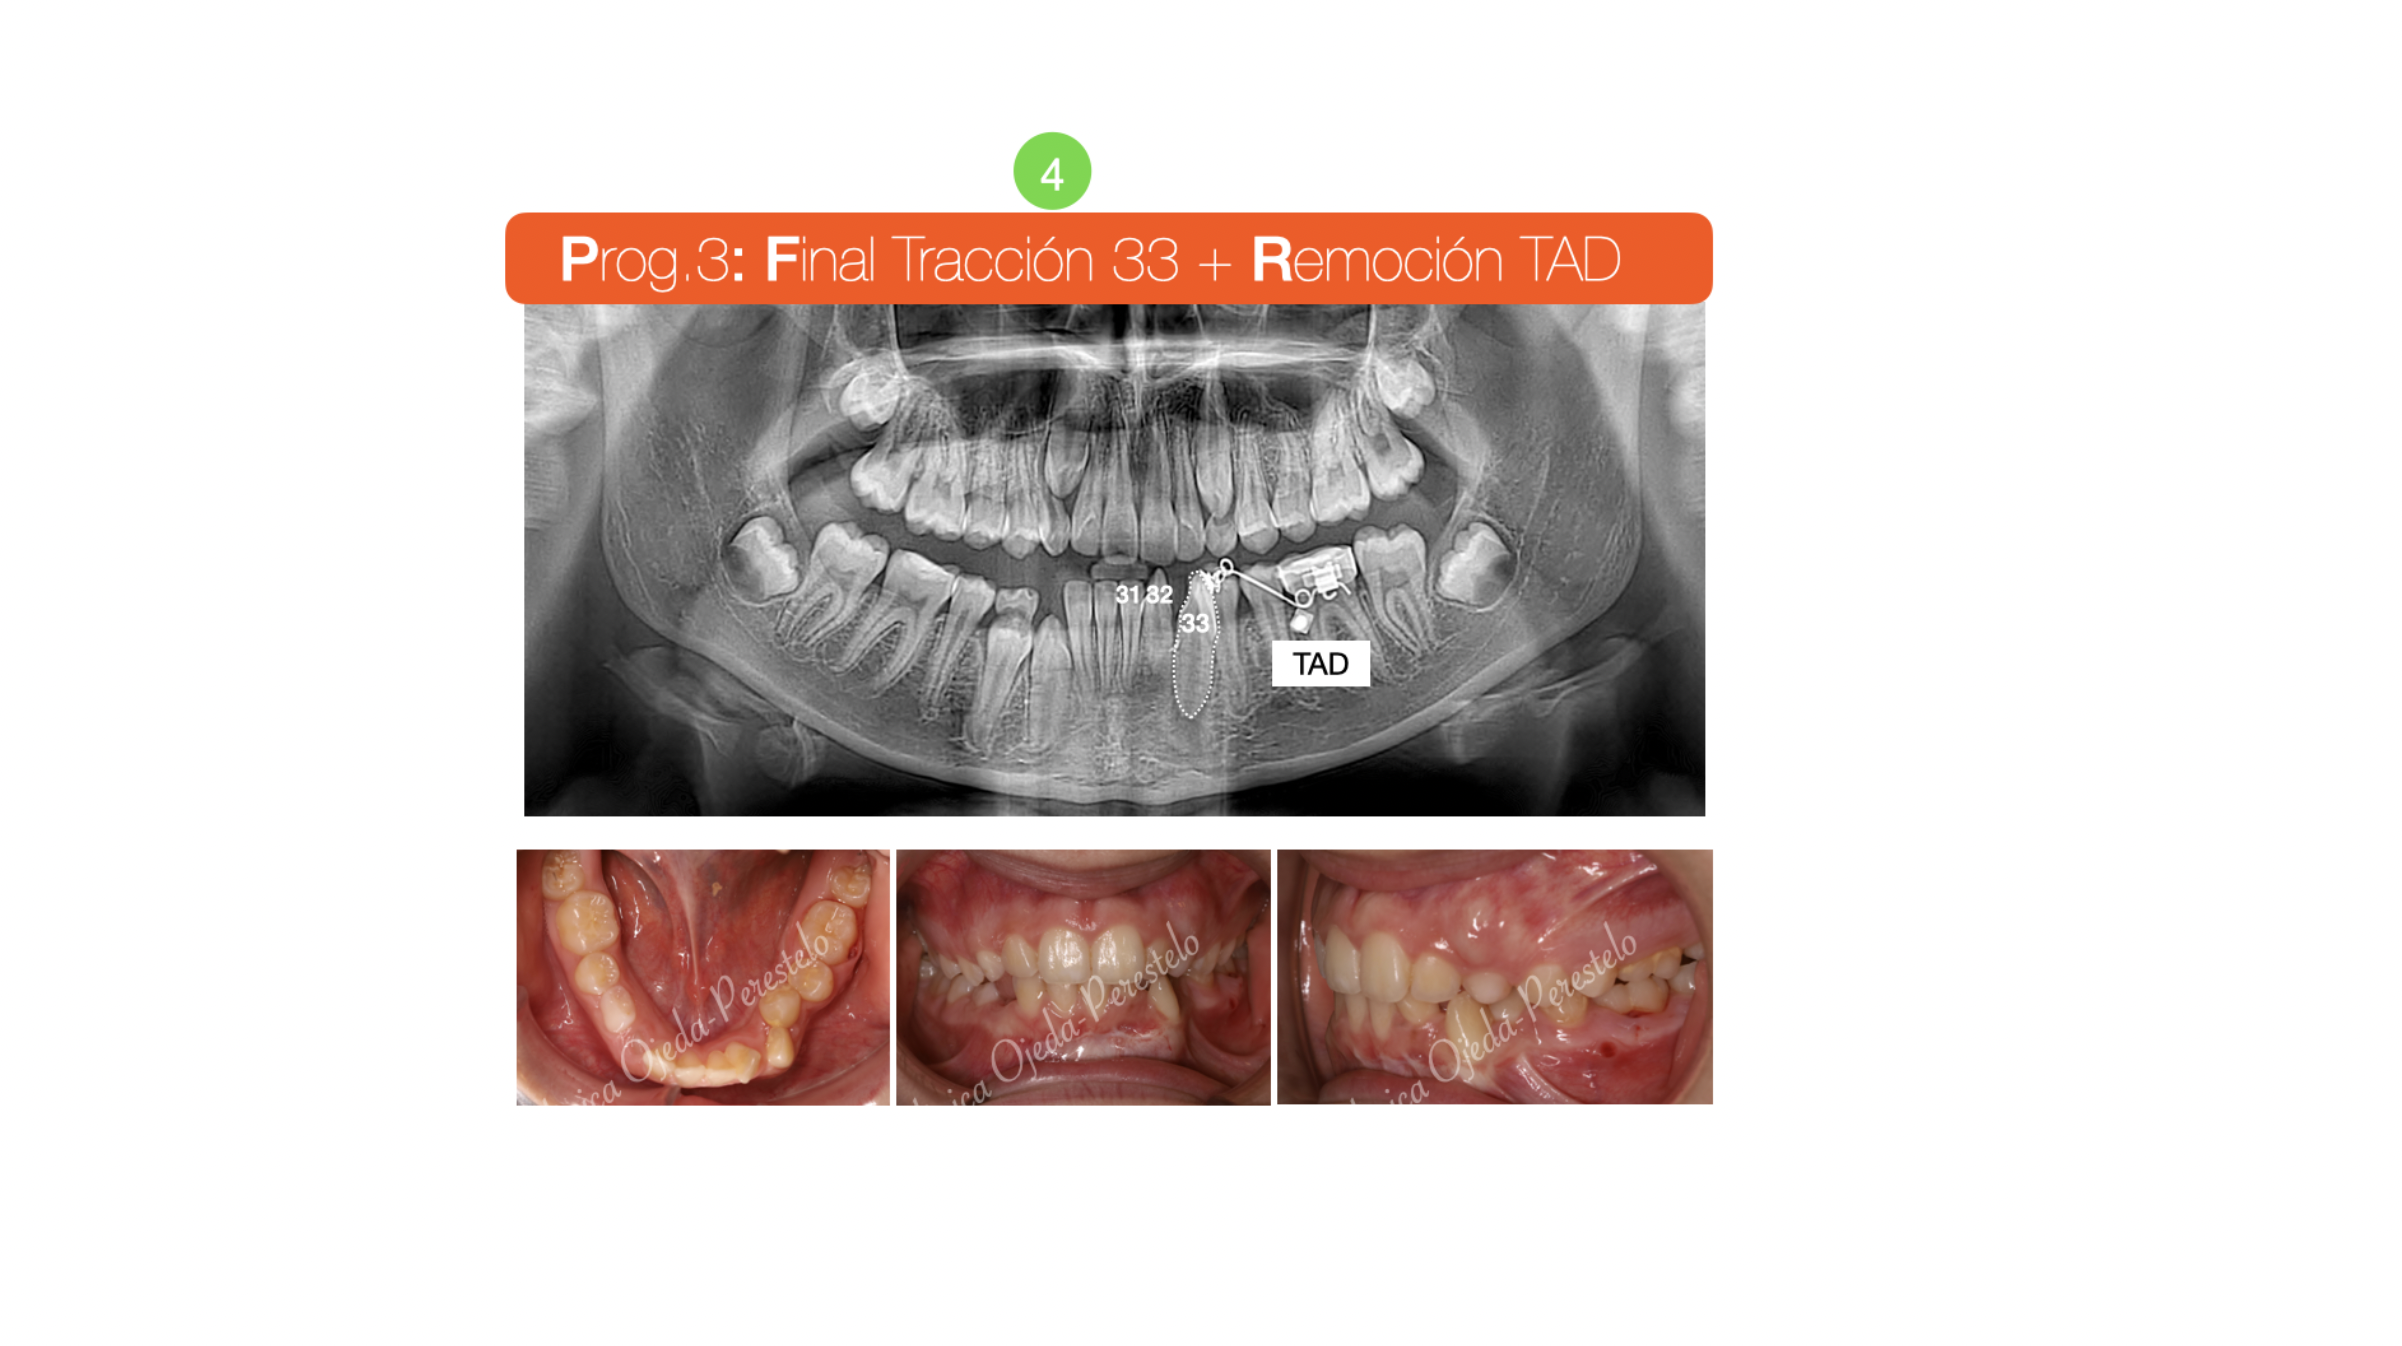

Tras la revaluación de la posición detallada, se decide realizar una fenestración al 33 e implementar un vector distal a efecto de no tocar las raíces de los incisivos inferiores durante su enderezamiento del 33.  El canino lleva adherido a su corona una cadeneta y se traiciona hacia un Microtornillo/TAD ( recubierto con resina azul en la imagen). Conforme va progresando el canino a su posición final, le vamos dotando al sistema de un vector extrusivo hasta que aparece en boca momento en el que ya podemos desinsertar el TAD.

Quisiéramos destacar que hoy en día los TADs nos han facilitado y simplificado mucho la reubicación de los dientes retenidos, desarrollando estrategias biomecánicas con un mínimo sufrimiento en los dientes adyacentes/apoyo en relación a los procedimientos tradicionales.